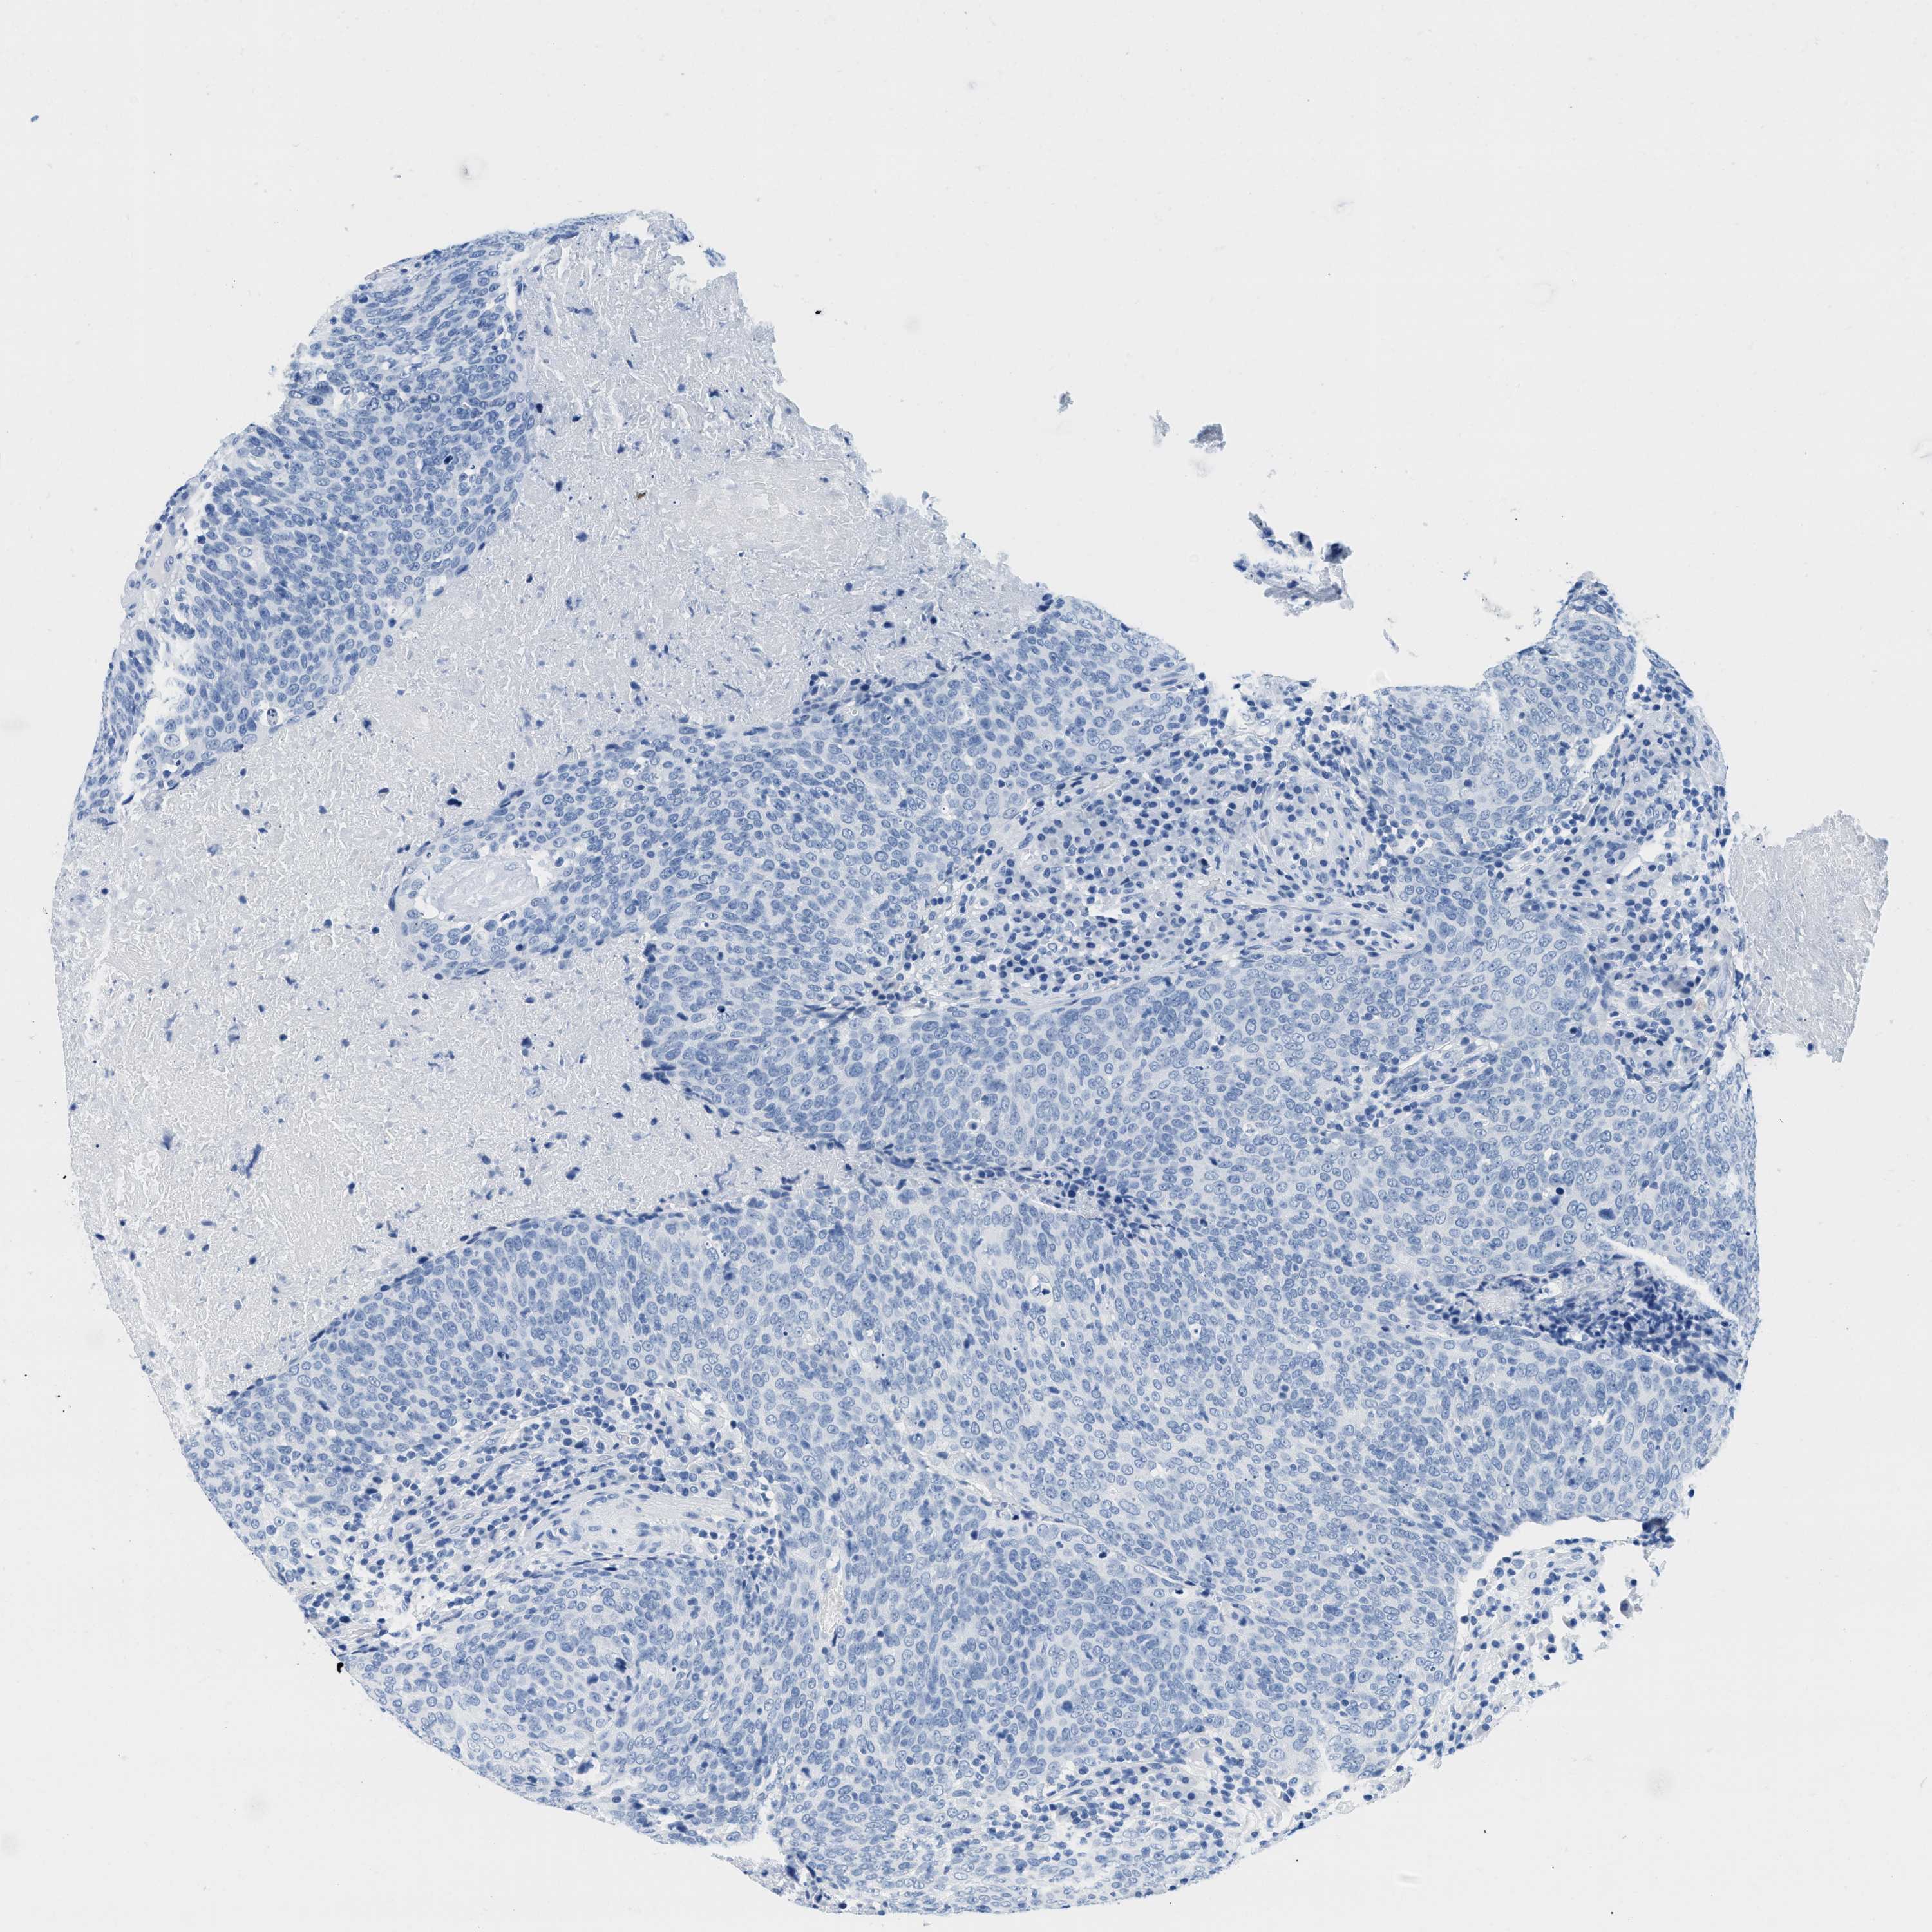

HEAD AND NECK CANCER - Protein expressioni

A mouse-over function shows sample information and annotation data. Click on an image to view it in a full screen mode. Samples can be filtered based on level of antibody staining by selecting one or several of the following categories: high, medium, low and not detected. The assay and annotation is described here.

Antibody stainingi

Antibody staining in the annotated cell types in the current human tissue is reported as not detected, low, medium, or high, based on conventional immunohistochemistry profiling in selected tissues. This score is based on the combination of the staining intensity and fraction of stained cells.

Each image is clickable and will lead to virtual microscopy that enables deeper exploration of all samples and also displays staining intensity scores, fraction scores and subcellular localization as well as patient and tissue information for each sample.

Antibody HPA054026

Antibody CAB010823

Antibody CAB016728

Antibody CAB036009

Staining

High

Medium

Low

Not detected

Intensity

Strong

Moderate

Weak

Negative

Quantity

>75%

75%-25%

<25%

None

Location

Nuclear

Cytoplasmic/membranous

Cytoplasmic/membranous,nuclear

Squamous cell carcinoma, NOS

Adenocarcinoma, NOS

Squamous cell carcinoma, metastatic, NOS

Adenoma, NOS